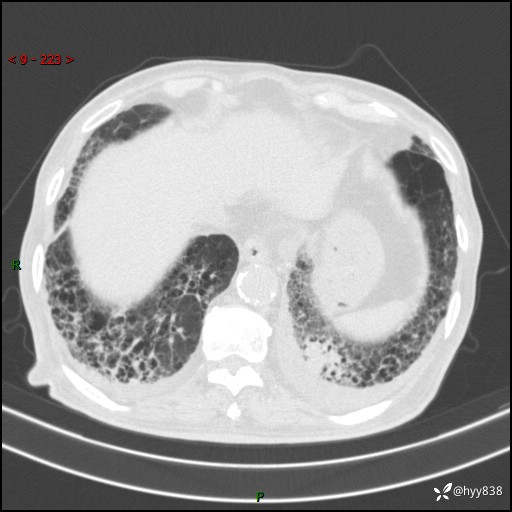

老年男性,间断咳嗽咳痰20余年,加重伴发热1天。呼吸科疑难病例讨论---结果公布

主诉:间断咳嗽咳痰20余年,加重伴发热1天

简要病史:家属代诉患者于20余年前无明显诱因出现咳嗽咳痰,痰为白色泡沫状,未行特殊治疗,不伴胸痛、胸闷、气喘、咳血等不适,1天前上午患者无明显出现发热,查体温39℃,伴咳嗽,咳痰无力,自行予以物理降温对症治疗,今晨2点左右再次出现发热,体温达40℃,自行服用复方氨酚烷胺对症治疗,凌晨3点左右复测体温38.2℃,现患者为求进一步诊治于今日就诊于我院门诊,行胸部CT提示双肺感染,遂以“肺部感染”收入我科。 患者本次起病来精神、食欲、睡眠欠佳,体力下降,体重无明显变化。

辅助检查:CT

临床诊断:感染

讨论:病变性质?

胸部CT平扫